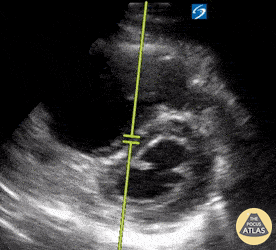

PSSX View. Septal Flattening is being demonstrated (D-sign) at the level of the papillary muscles and chordae tendinae visible in both the left ventricle and right ventricle. The right ventricle is demonstrating significant dilation in the setting of increased pressures secondary to a saddle embolus. Moudi Hubeishy @moudihubeishy